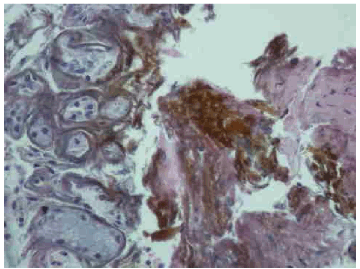

Examination was remarkable only for auscultatory wheeze over the right mid zone anteriorly and right base posteriorly. Hematologic investigations showed microcytic anemia with hemoglobin of 11.1 g/dL and mean corpuscular volume, (MCV) of 73 fL. Chest radiograph revealed a large left hiatal hernia but was otherwise unremarkable. A contrast chest computed tomography (CT) scan confirmed the hiatal hernia but was devoid of any other abnormality. Fiberoptic bronchoscopy done within 24 hours revealed that the tracheal and bronchial mucosa was erythematous and edematous. The mucosa at the bifurcation of the right middle and lower lobe and in the right lower lobe was most affected and appeared corrugated, ulcerated, friable and bled easily (Figure 1). The area was lavaged and thick brownish secretions were suctioned. Bronchial biopsy at the level of right middle and lower lobe carina and from the right lower lobe revealed features of mucosal burn with edema and inflammation and stained positive for iron with prussian blue stain (Figure 2, 3).

Figure 3: Photomicrograph shows iron deposition and inflammation on airway biopsy (H&E, x40).